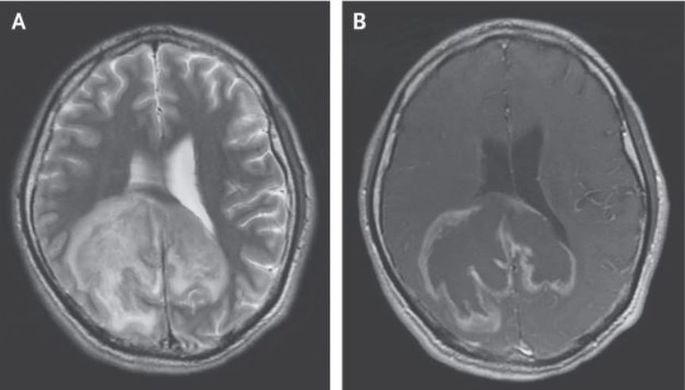

Сообщается, что в 2015 году в центр детской психоневрологии Москвы поступила девочка в возрасте пяти лет, которая не могла ходить, ползать и разговаривать, плохо видела и не проявляла интереса к окружающему миру. Ее родители рассказали, что в развитии девочки не было нарушений, пока ей не исполнилось 2,5 года, после чего у нее стал сокращаться словарный запас, сама она стала неуклюжей, а к пяти годам перестала ходить.

Первоначальным предположением ученых было наличие у девочки синдрома Ретта, который возникает только у женщин, и связан с мутацией в гене MECP2, однако проверки состояния нервной ткани показали, что это не так. В ходе дальнейших исследований, оказалось, что причиной происходящего с девочкой была ранее неизвестная мутация в гене MFSD8, который отвечает за перенос белков и других молекул внутри лизосом.